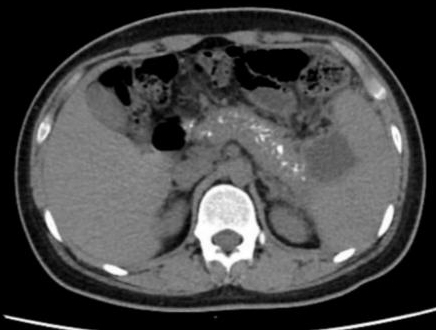

患者男,17岁,主因“反复腹痛2年,加重伴发热2 d”来诊。患者于2019年起常于进食后出现腹部不适、纳差、腹痛,服用“胃药”对症处理后可好转,此后反复发作,频繁时半月发作一次。2020年9月下旬患者进食油腻食物后出现脐周及左中腹部胀痛,无恶心、呕吐,当地医院腹部CT提示:慢性胰腺炎急性发作,经对症治疗后2~3 d好转,此后每月有类似症状发作一次。2021年1月18日到本院基本外科门诊查胰腺功能,血清淀粉酶73 U/L,脂质624 U/L; 血钙正常; 血脂4项正常; 检查肿瘤指标,CA-125: 46.9 U/mL(升高),余为阴性; 甲状旁腺素正常; 血清IgG四项:IgG3 154 mg/L(降低),IgG4 1 600 mg/L(升高)。腹盆CT示胰腺多发钙化,胰尾囊肿形成(图 1)。1月22日患者进食汤面后出现腹部不适、纳差、乏力。1月24日晨起后出现腹部剧烈疼痛,伴发热,最高37.6℃,无恶心呕吐,无腹泻,于本院急诊就诊查血象正常,超敏C反应蛋白142.15 mg/L,胰腺功能:血清淀粉酶130 U/L, 脂质1 127 U/L。行腹盆CT检查示:胰腺饱满伴多发钙化,胰周脂肪密度稍增高,可见多发索条影,符合慢性胰腺炎改变(图 2)。予厄他培南抗感染及抑酸、补液等支持治疗后症状略好转,于1月26日收入本院急诊留观继续治疗。既往史:早产儿(32周),右桡骨小头骨纤维瘤术后,过敏性哮喘。个人史:否认饮酒史。家族史:父母体健,无其他特殊情况。

图 2 患者2021-01-24腹部CT